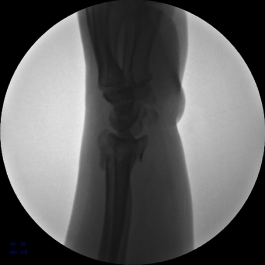

2.安装外固定架,调节螺母纵向牵拉,初步恢复桡骨高度

3.背侧穿针撬拨,继续恢复桡骨高度